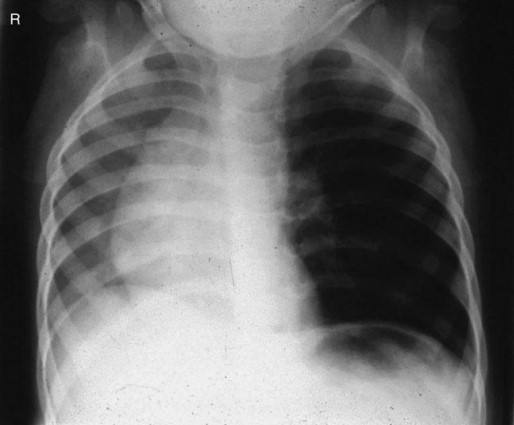

Common X-ray Findings: